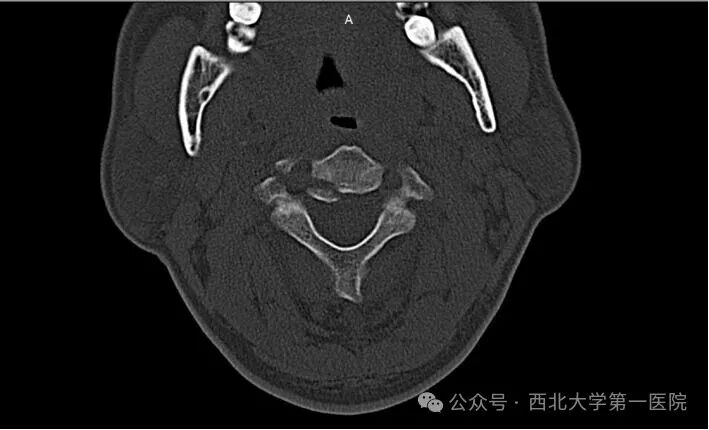

本例患者张先生(化名)遭遇汽车追尾事故。事故发生时,巨大的暴力瞬间作用于颈椎,导致其颈部剧痛、活动严重受限。被紧急送至西北大学第一医院后,急诊颈椎CT三维重建检查明确诊断为Hangman骨折(Levine - Edwards分型Ⅱ型)。影像资料显示,张先生的第二颈椎(枢椎)两侧椎弓根骨折,椎体向前移位,颈椎稳定性遭到严重破坏。脊髓作为人体的“神经总电缆”,在骨折断端间承受着巨大的压迫和牵拉风险,随时可能引发呼吸心跳骤停或四肢瘫痪等严重后果,情况万分危急。

患者伤后CT冠状面显示,C2椎体双侧椎弓根均有骨折,属于不稳定的Ⅱ型骨折。对于此类患者,时间就是生命,速度关乎功能恢复。脊柱外科(骨科三病区)迅速启动应急预案,为患者佩戴头颈胸支具严格制动,并立即组织多学科术前讨论。保守治疗虽有一定尝试空间,但对于这种明显移位的Ⅱ型骨折,长期卧床牵引不仅愈合率低,还存在滑脱加重的高风险,犹如一颗“定时炸弹”。经过严谨、审慎的评估,医疗团队最终决定为张先生实施“后路颈椎切开复位、C2椎弓根螺钉 + C3侧块螺钉钉棒系统内固定融合术”。